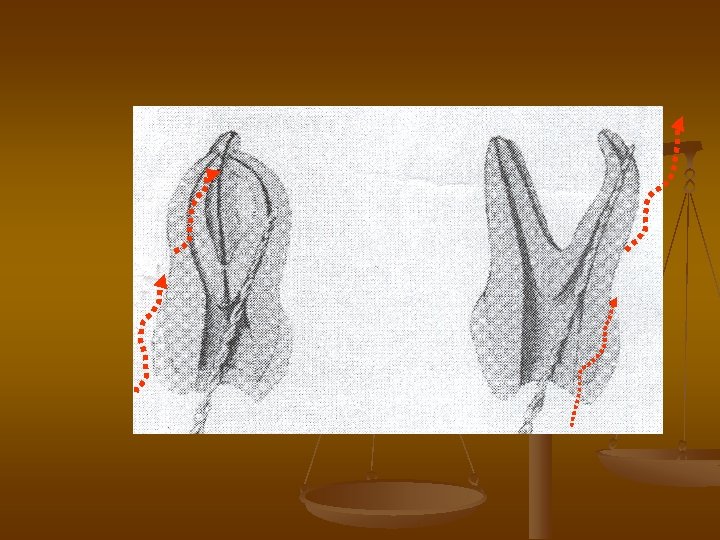

Surplus expansion of the channel in average one third on internal curvature root ( stripping ) n n The Reason. The Underestimation of the curvature of the channel and work in curved channel it is not enough curly instrument. The Preventive maintenance. To avoid the surplus extension in small curvature , follows beforehand to bend the files in accordance with curvature of the channel, when n n processing to use anti perforation technology , when file snuggles to big curvature. Avoid this complications under премениении gimlet Safety hedstroem and fine files possible. follow. Ushould Anecessary Avoiding the surplus extension narrow, twisted channel: their follows expand not more on 2 -4 sizes from initial width.

Ledging equipment in Portenko canada additional gouge n The Reason. The Underestimation of the curvature of the channel and work in curved channel it is not enough curly instrument.